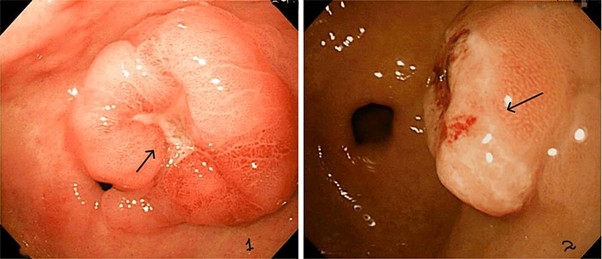

This article has been retracted in accordance with medtigo Journal of Medicine policy (https://journal.medtigo.com/journal-insights/#pub_inte_and_retra). In a post-publication review, concerns were identified regarding permission for use and the copyright status and of certain images used in the article. The author failed to respond to requests for confirmation of permission to use the images in their submission and in our publication. OR The author was unable to provide confirmation of permission to use the images in their submission and in our publication. As a result, the Administrative Editor of the medtigo Journal of Medicine has determined that retraction of this article is necessary to comply with ethical standards and to maintain the integrity of the scientific record.